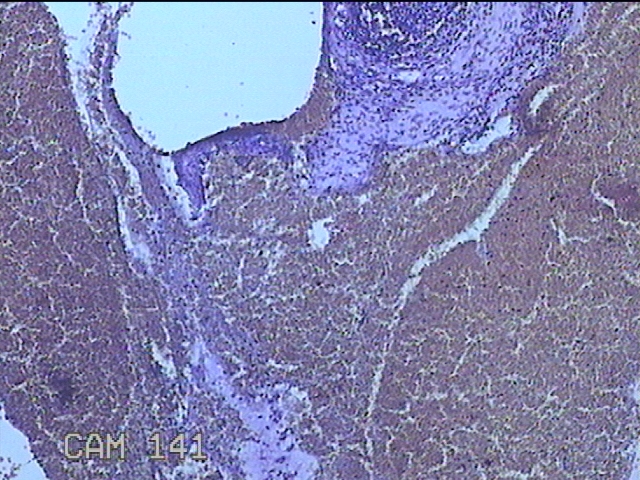

性别

女

年龄

36岁

临床诊断

子宫内膜炎

一般病史

经期延长1月。

标本名称

子宫腔内膜

大体所见

灰白暗红色不规则碎组织2.5x2.3x0.7cm一堆。